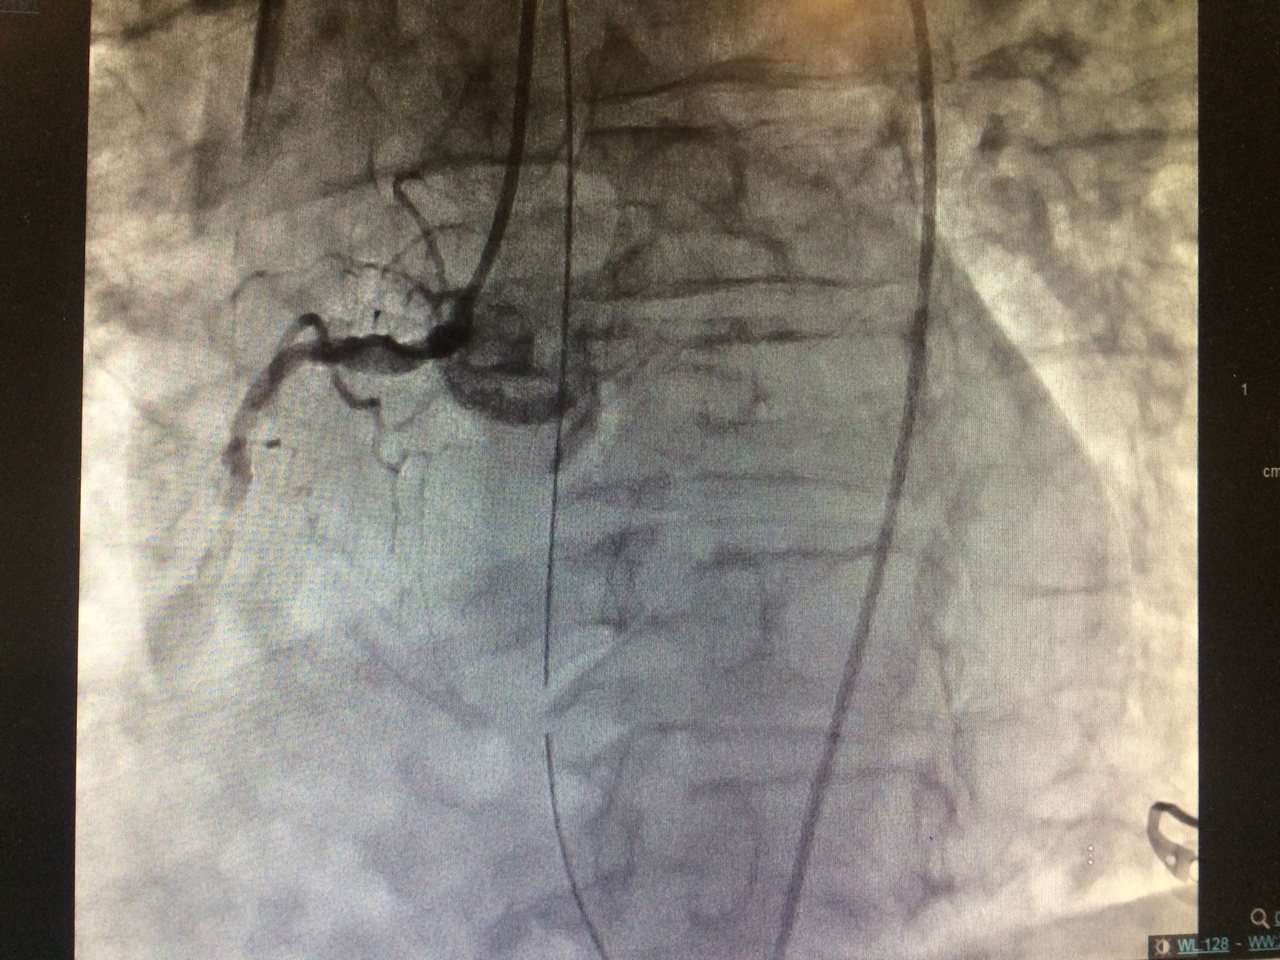

Vous transportez le patient en Fast Track vers la salle de coronarographie la plus proche.

Voici le résultat de l’examen

Occlusion aiguë thrombotique de la coronaire droite, flux TIMI 0 (thrombolysis in myocardial infarction zero)

Traitement de référence dans le STEMI (

ST-elevation myocardial infarction) : revascularisation par stent actif

Le traitement de référence est la revascularisation par voie percutanée, en urgence, la plus précoce possible, avec implantation d’un stent actif au niveau de la lésion coupable.

Vous retenez donc le diagnostic d’infarctus inférieur Killip 1, de prise en charge tardive sur occlusion de la coronaire droite. Le patient est thrombo-aspiré et bénéficie de l’implantation d’un stent actif sur la coronaire droite moyenne. Le résultat angiographique est optimal avec rétablissement d’un flux TIMI 3. L’artère interventriculaire antérieur et circonflexe sont athéromateuses, sans lésion significative par ailleurs.